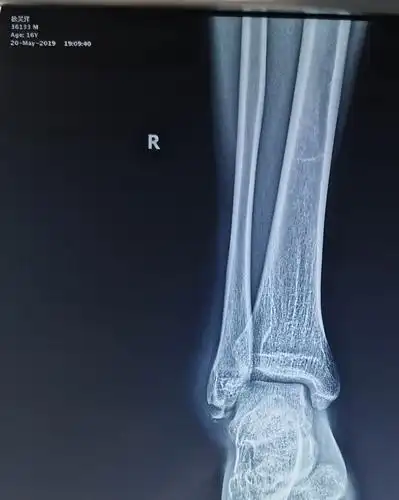

一例腓骨下极撕脱骨折